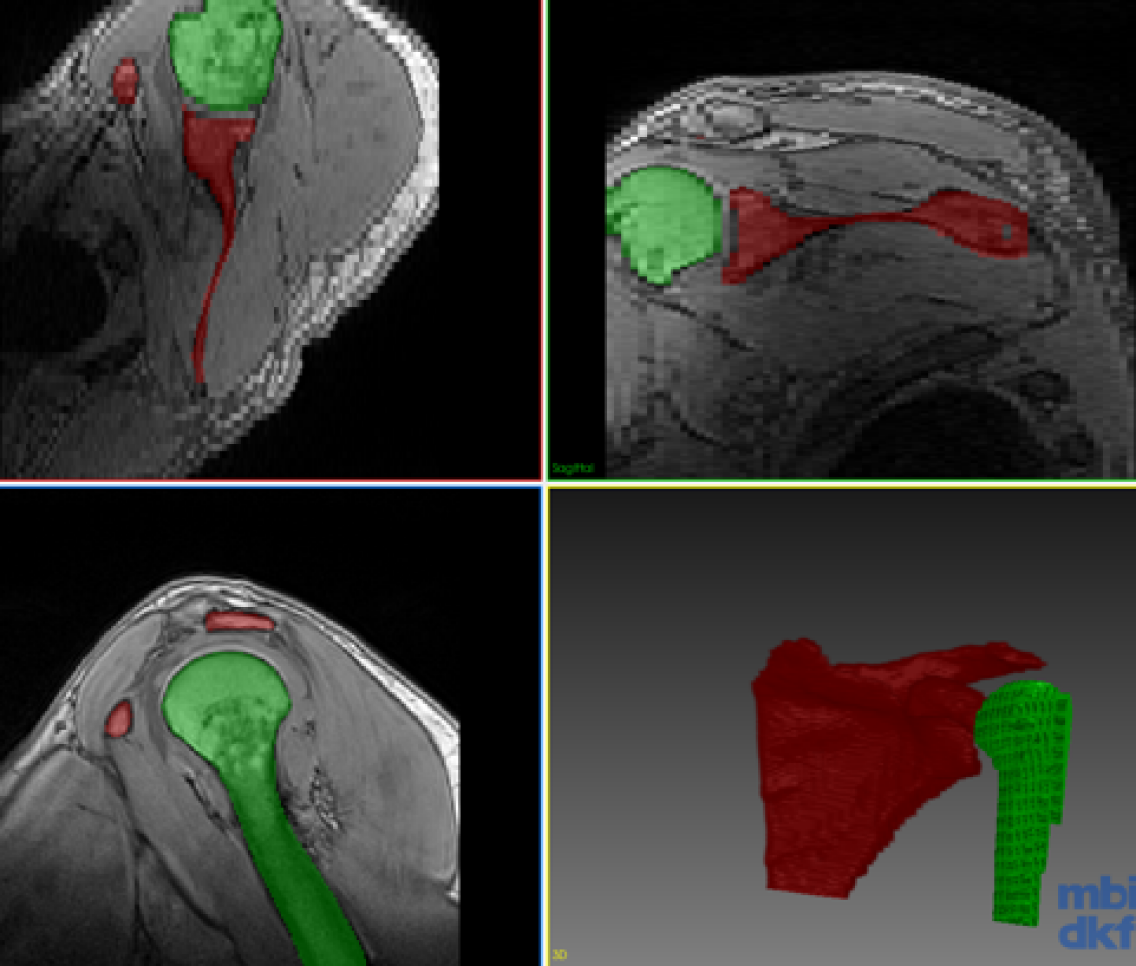

Refer to caption

(c) HumSeg Case 2

(d) CoRiSeg Case 2

Figure 3: Segmentation of the test volume with different methods.

Our experimental dataset consists of 9 Dixon sequences of left shoulder collected with 1.5 Tesla at resolution of 0.91 mm x 0.91 mm x 3 mm, corresponding to 192x192x64 voxel resolution. Humerus and scapula bones were annotated by an expert. Our goal is to combine knowledge from different data for a network that can segment both anatomical structures. We evaluated our proposed method for the three scenarios shown in the table in Fig. 2. One volume each was fixed randomly for validation and testing each of all scenarios. The first scenario (Case 1) tests a typical setting where different anatomies were of interest and thus annotated in separate studies. The second scenario (Case 2) aims to observe advantages of incremental training with minimal effort, i.e., incrementally annotated data, giving insight on an extreme case where a single volume annotation is provided. The last scenario (Case 3) studies the feasibility of combining learned segmentation information from different anatomy and images of different contrast. The methods were implemented with Tensorflow [14] and ran on an Nvidia Titan X GPU. Proposed network is implemented in 2D, hence 646464 image samples per volume given in Fig. 2. For a fair comparison, we fixed all parameters across different models to kcsubscript𝑘𝑐k_{c}==505050, krsubscript𝑘𝑟k_{r}==303030, α𝛼\alpha==0.50.50.5, tMCsubscript𝑡MCt_{\mathrm{MC}}==292929, batch size of 8 images, and trained all models for 1000 epochs. Used network (cf. Fig.1) has a first convolutional layer with 64 filters and the amount of filters double at every coarsening level. Each convolutional layer is proceeded with a batch normalization and ReLU activation. For CoRiSeg, we use a VGG16 network [7] pre-trained on ImageNet [13]. While a VGG trained on a medical image set would be expected to provide more accurate dcontsubscript𝑑contd_{\mathrm{cont}} score, training set of ImageNet is not matchable by any annotated medical database. We used Dice similarity coefficient and average symmetric surface distance for evaluating segmentation performance across tested methods (cf. Table 1). We compared our proposed methods: LwfSeg with its extensions with exemplar sets AeiSeg and CoRiSeg. Upper bound cases are presented with networks trained on only a given anatomy/dataset, i.e., without any incremental learning and hence without the need to preserve “old” (extra) information. We also show results from finetuning for comparison, although catastrophic forgetting is a known problem. In Fig. 3, we showcase qualitative results from different scenarios (cf. table in Fig. 2).

As seen, with finetuning, the shared network body gets re-tuned to adapt to the new incremental data, almost completely forgetting the initial classes. Proposed segmentation extension of learning without forgetting (LwfSeg) performs relatively well in all cases. For every scenario, both proposed methods using exemplar sets either outperform or achieve performance as close to LwfSeg for the old class. CoRiSeg achieves the highest Dice score for the old data, suggesting that for selecting exemplars the maximum set coverage over content distance is more effective than averaging at abstraction-layer (AeiSeg). In addition, in Case 2, where the incremental dataset is severely handicapped, both LwfSeg and CoRiSeg surprisingly outperform HumSeg. While it is expected for a network trained on 1 volume (64 images) to perform poorly, incremental networks are seen to achieve higher segmentation performance, suggesting that shared-body layers potentially learned to extract bone-generic knowledge. Should this be shown for a wider range of bone structures, it would be critically relevant for orthopedic applications in the future. When the incremental dataset is introduced from a different imaging sequence in Case 3, one can see the great advantage of keeping exemplar samples; i.e., 28.8% increase in Dice score of CoRiSeg compared to LwfSeg. While the performance difference is less obvious for the new class, the change in old class scores suggests distillation loss to have provided false “guidance” on the new dataset with LwfSeg, i.e. trying to retain old class segmentation performance without any exemplar samples. Since finetuning does not need to remember the appearance of humerus (bone) in the other image modality, it outperforms with scapula in Case 3. We expected VGG trained for object classification (on ImageNet) to select better exemplar images for our task. Indeed, compared to CoRiSeg, using the UNet trained by us for dcontsubscript𝑑contd_{\mathrm{cont}} yielded 1.6%, 0.7%, and 0.07% worse Dice, respectively, for each Case.

Note the high average symmetric surface distance in some of the proposed incremental methods, i.e., AeiSeg and CoRiSeg in Case 2; LwfSeg in Case 3. These are due to small blobs of false positives far from the target anatomy (cf. Fig. 3). These blobs could possibly be removed with a trivial post processing step (e.g. morphological operations, largest connected region, conditional random fields, user input), which is beyond the objective of this paper. Additional randomized hold-out test sets for Case 3 showed little variation (\approx2% Dice) in results, while the proposed AeiSeg and CoRiSeg were still over 27% Dice better than LwfSeg in retaining old class info. We will conduct extensive evaluations in future.